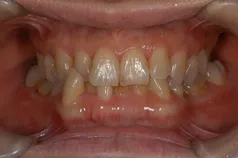

[症例]

矯正治療を行っています。

治療前は上下の歯が反対になっている所もあり、上の歯の真ん中から2本目の歯は矮小歯と言って、平均より小さな歯のため上唇が引っ込んで見えます。

インビザラインでマウスピース矯正後、オフィスホワイトニングを行い、矮小歯はラミネートベニアで修復しました。

綺麗な歯並びになるとともに、上顎の歯列のアーチが広がって、上唇がやや前方に出ることで自然な口元になりました。

- 治療期間: 1年6ヶ月

- 治療回数: 10回

- 費用: 120万円

- デメリット:治療後に矯正の後戻り防止のためのマウスピースを使用しなければならない